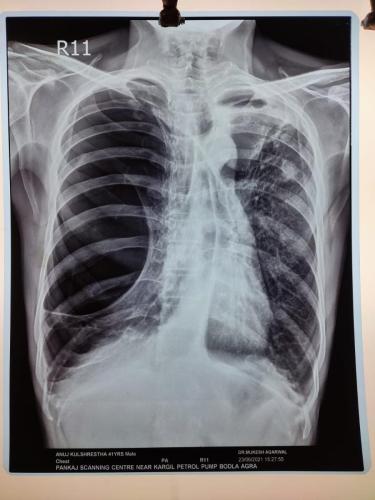

Photo Gallery Dr. Monika Gupta - Photo Gallery 7 5 2 8 6 Dr. Atul Kumar Gupta - Photo Gallery « ‹ of 3 › » Video Gallery